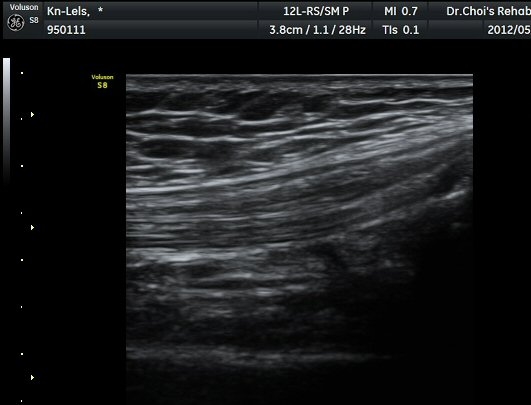

»çµÎ±Ù ÈûÁÙ Á¾´Ü¸é°Ë»ç¿¡¼­ ÈûÁÙÀÇ ºñÈİ¡ °üÂûµÈ´Ù9±×¸² 1, 2).

½½°³°ñ¾Æ·¡ ÈûÁÙ Á¾´Ü¸é°Ë»ç¿Í Ⱦ´Ü¸é°Ë»ç¿¡¼­ ÈûÁÙÀÇ ºñÈİ¡ °üÂûµÇ°í(±×¸² 3, 4).

ÈûÁÙÀÇ ºñÈÄ´Â °ÇÃø(±×¸² 5)°ú ºñ±³ÇÏ¸é ¶Ñ·ÈÇϰí, ÆÄ¿öµµÇ÷¯°Ë»ç¿¡¼­ ÈûÁÙ³»¿¡

Ç÷·ùÁõ°¡µµ È®ÀδϵȴÙ(±×¸² 6, 7).